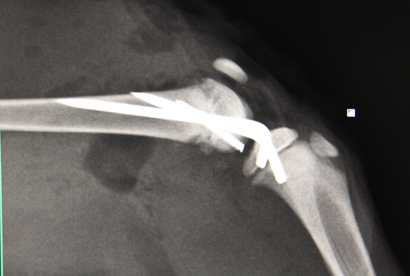

Der süße Morris hatte auf der Pflegestelle einen kleinen Unfall und hat sich unglücklicherweise ein Hinterbeinchen oberhalb des Knies gebrochen.

Er wurde natürlich sofort operiert und hat nun Stifte im Knochen, die alles zusammenfügen und gerade halten. Der kleine Mann macht sich prima, erträgt tapfer das Dasein als Patient und geht schonend mit seinem Beinchen um.

Bis er wieder hergestellt ist, wird aber einige Zeit ins Land gehen. Die OP-Wunde ist gut verheilt, die Fäden mittlerweile gezogen und der Süße kann sein Beinchen schon wieder ein bisschen benutzen.

Wir hoffen nun, dass nach einigen Wochen die Stifte entfernt werden können, auch dann alles gut hält und auch das Bein normal weiterwächst.